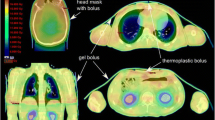

The planning target volume (PTV) included the entire body trimmed to 3 mm below the body. Furthermore, the PTV was divided into two structures, which are the PTV-BODY and the PTV-ARM (Fig. 1). These structures were 14 cm from the center in the left–right direction. The OARs included the lens, lungs, kidneys, and testes, which were excluded from the PTV.

Splitting of the CT images into the cranial and caudal parts required a dosimetric alignment of these two body parts. The cranial part was created using the head-first position from the vertex of the skull to the upper thigh, while the caudal part was created using the feet-first position from the toes to the lower thigh because the PTV length exceeded the couch travel capability of the Halcyon™ linac. The overall PTV was split into seven segments with subsequent multi-isocentric planning. Each segment was divided at 13 cm from the center in the cephalad direction because of the capacity of the collimators. There were thirteen isocenters. Figure 2 shows the seven segments of the PTV with thirteen isocenters. Two to four full arcs of VMAT were applied (gantry angle, 181–179° clockwise and 179–181° counterclockwise; collimator angles, 270°, 280°, and 359°) for each isocenter (see Additional file 1: Table S1 for beam arrangement of VMAT-TBI with Halcyon™). The control point spacing was 2° from the angular separation. The beam arrangement was set to meet our goal for PTV coverage of D95% > 80% [23]. The collimator angle was fixed to maximize the field size in each segment. The maximum dose rate was 600 monitor units (MU) per minute. The dose rate was established using the MU calibration geometry setting (isocentric, 90 cm SSD) of the linac and could not be changed by the user.

The DVH parameters are summarized in Table 2 and Fig. 3. Figure 4 shows the dose distributions. The Dmax of the whole body was 15.7 Gy (130%). The PTV D98%, D95%, D50%, and D2% were 8.9 Gy (74.2%), 10.1 Gy (84.2%), 12.6 Gy (105%), and 14.2 Gy (118%), respectively. The HI was 0.42. In terms of OARs, the Dmean of the lungs, kidneys, lens, and testes were 9.6 Gy, 8.5 Gy, 8.9 Gy, and 4.4 Gy, respectively. The Dmax of the testes was 5.8 Gy. The V12Gy of the lungs and kidneys were 4.5% and 0%, respectively. The V5Gy of the lungs was 100%. The DVH parameters met our goal for the target and almost all OARs, except for the V12Gy of the lungs (Table 2). Additionally, the total MU was 8996.